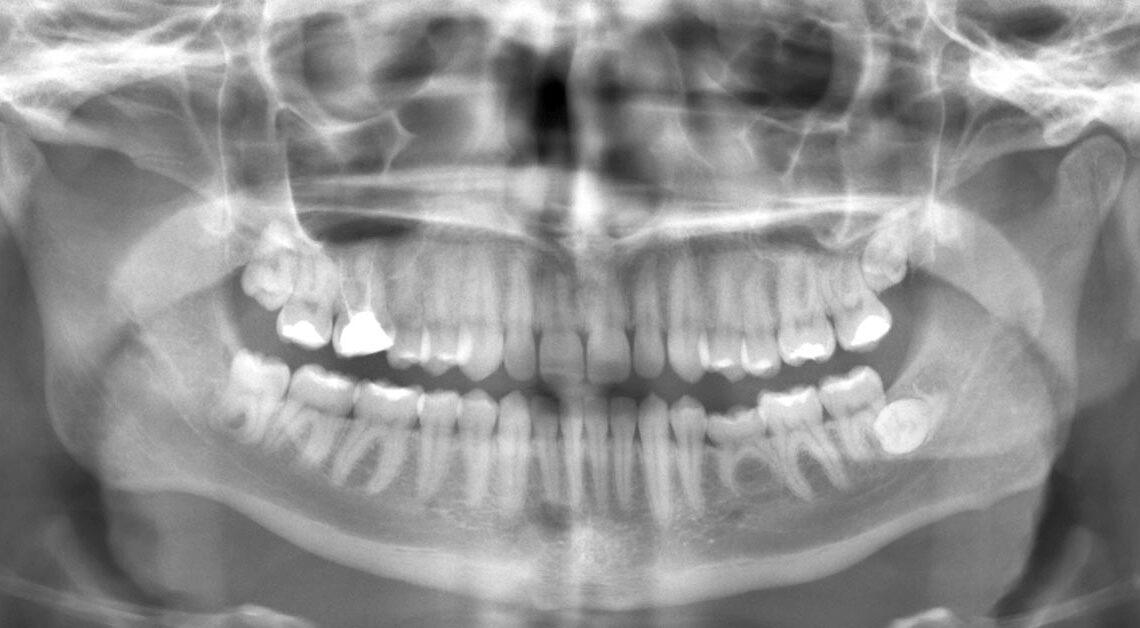

Os dois tipos de radiografias mais utilizados na odontologia são as panorâmicas e as periapicais.

Radiologia Panorâmica

A radiografia panorâmica é um dos mais importantes mecanismos.

É usada amplamente, pois possibilita determinar a situação do osso na face do paciente, bem como a arcada dentária, em uma só tomada radiográfica.

É de grande facilidade, já que o filme é colocado fora da boca do paciente.

É indicada para avaliar doenças e anomalias dentais. São produzidas imagens clinicamente aceitáveis pelos cirurgião-dentista por meio dos equipamentos de radiografia panorâmica. .

Quando o posicionamento do paciente está correto e, caso haja p uso de filmes radiográficos, a revelação precisa ser feitas com uso correto.